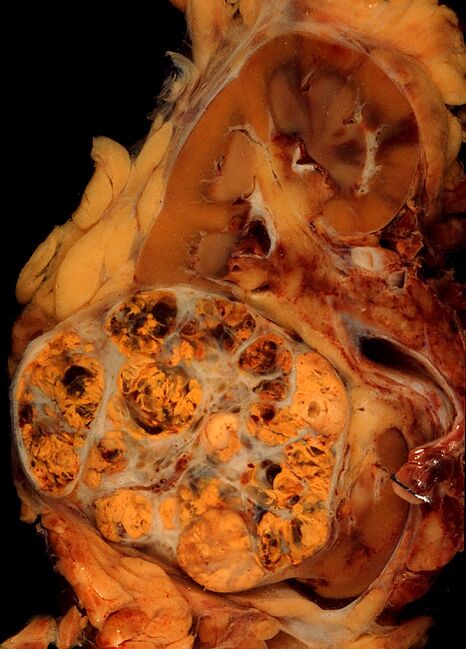

| Микрофотография, демонстрирующая наиболее частый тип рака почки — светлоклеточный (окраска гематоксилином и эозином) | |

Рак по́чки — злокачественная опухоль почки, которая чаще всего представляет собой карциному и развивается либо из эпителия проксимальных канальцев и собирательных трубочек (почечноклеточный рак, ПКР), либо из эпителия чашечно-лоханочной системы (переходноклеточный рак)[3].

Почечноклеточный рак представляет собой ведущую разновидность злокачественных опухолей, локализующихся в почке (хотя метастазы почечноклеточного рака могут поражать другие органы). У взрослых доля почечноклеточного рака среди первичных злокачественных опухолей почки составляет 80—85 %[4]. По другим сведениям, на почечно-клеточный рак приходится примерно 90 % всех злокачественных опухолей почки[5].